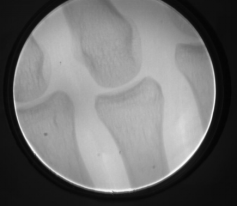

7:拍摄效果图